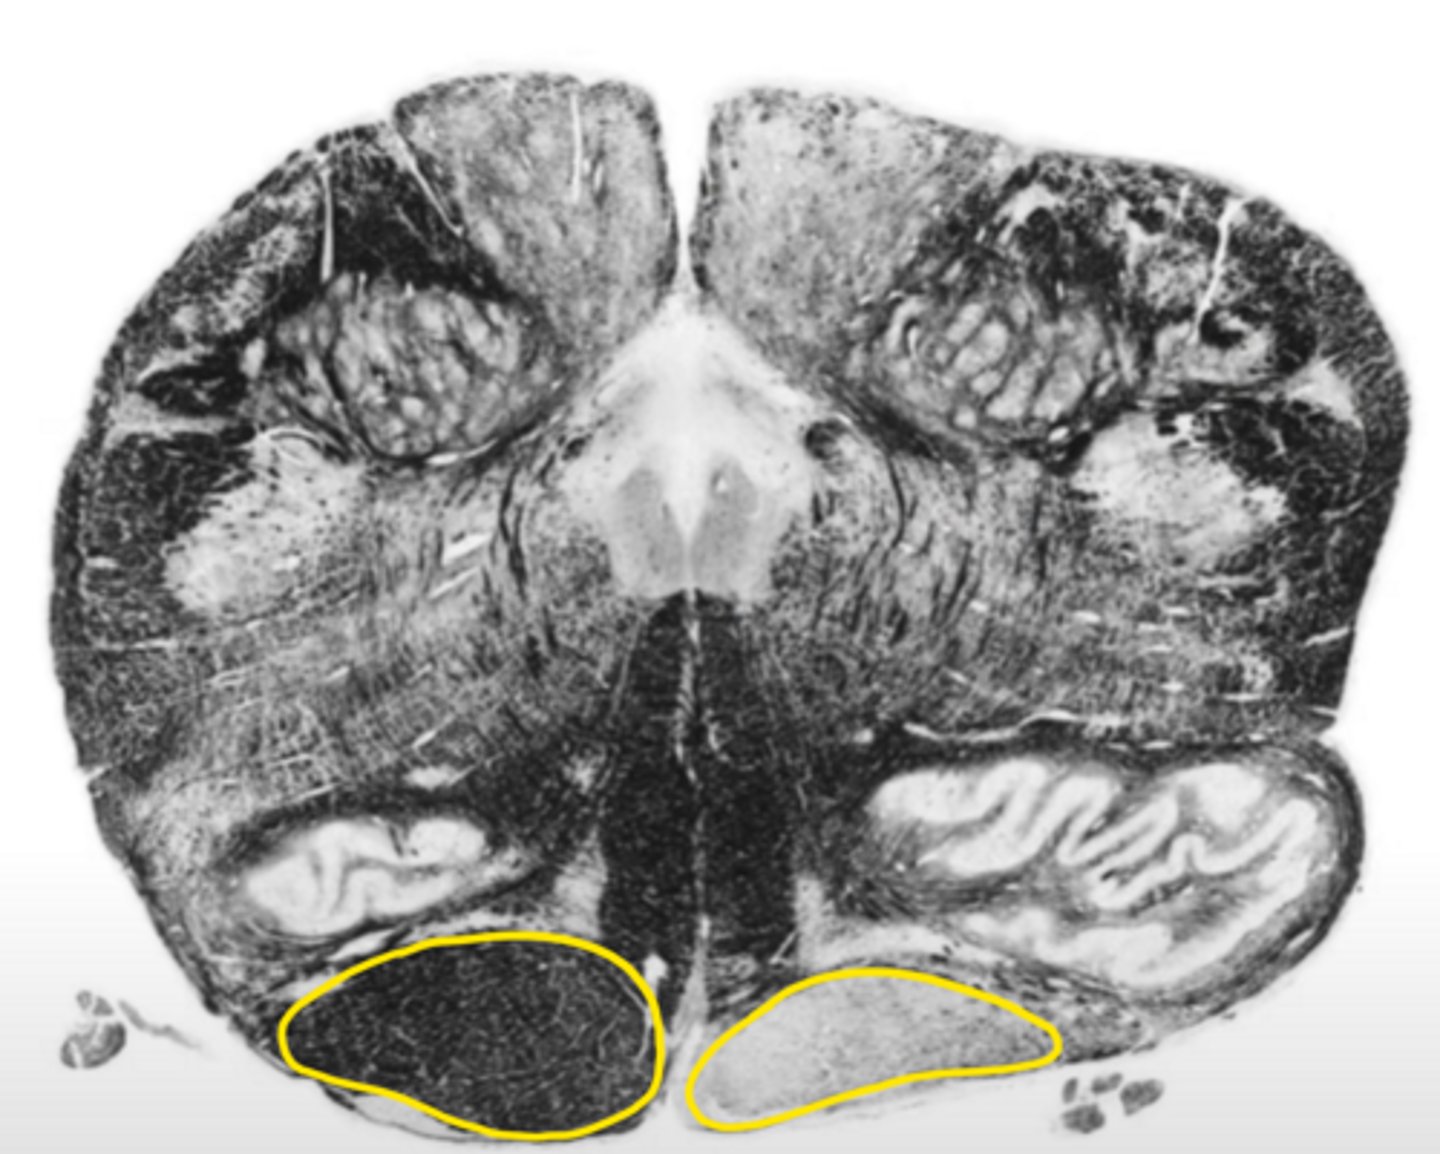

open medulla

ID the brainstem level

closed medulla